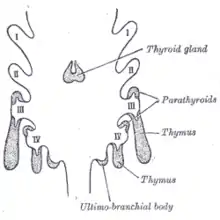

In the early development of the human embryo, a series of five pharyngeal arches and four pharyngeal pouches form that give rise to the face, neck, and surrounding structures. The pouches are numbered such that the first pouch is the closest to the top of the embryo's head and the fourth is the furthest from it. The parathyroid glands originate from the interaction of the endoderm of the third and fourth pouch and neural crest mesenchyme.[5] The position of the glands reverses during embryological development. The pair of glands which is ultimately inferior develops from the third pouch with the thymus, whereas the pair of glands which is ultimately superior develops from the fourth pouch. During embryological development, the thymus migrates downwards, dragging the inferior glands with it. The superior pair are not dragged downwards by the fourth pouch to the same degree. The glands are named after their final, not embryological, positions.[9] Since the thymus's ultimate destination is in the mediastinum of the chest, it is occasionally possible to have ectopic parathyroids derived from the third pouch within the chest cavity if they fail to detach in the neck.

Gross pathology of a parathyroid gland (white arrow), next to the thyroid gland Scheme showing development of branchial epithelial bodies. I, II, III, IV. Branchial pouches.

Scheme showing development of branchial epithelial bodies. I, II, III, IV. Branchial pouches.